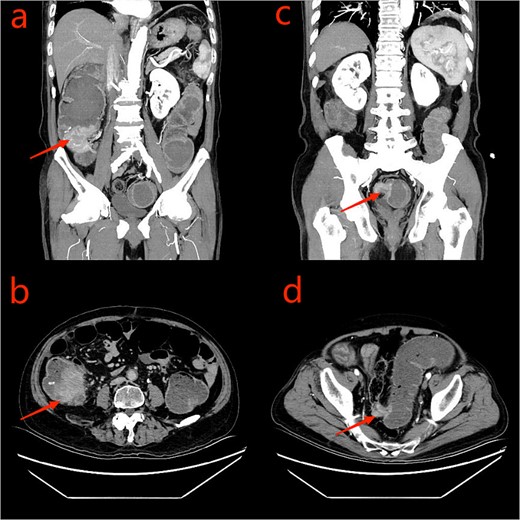

A 75-year-old male patient was admitted to the Department of Hematology due to small B-cell lymphoma. The patient had been experiencing incomplete intestinal obstruction for nearly 1 year and had been self-medicating with diarrhea-inducing medication obtained outside the hospital. During hospitalization, the patient exhibited a marked decline in appetite, accompanied by cessation of bowel movements, nausea, and vomiting. The patient weighed 85 kg, stood at 1.68 m tall, and had a body mass index of 30.12 kg/m2. He had no history of smoking, alcohol consumption, or surgery. Physical examination: the patient’s body temperature, heart rate, and blood pressure were normal, with abdominal distension, scattered abdominal tenderness without obvious rebound pain, and drumming sound on abdominal percussion. Laboratory tests: platelets, tumor markers CEA, the rest showed no abnormality. Chest computed tomography (CT) showed a few infection foci in the lungs, with no metastatic foci observed. Enhanced CT scanning of the abdomen revealed tumors in the sigmoid and ascending colon, with significant thickening observed in the proximal sigmoid colon tumor (Fig. 1). Colonoscopy revealed complete obstruction of the sigmoid colon (Fig. 2).

CT scan of the abdomen and pelvis: a: ascending colon tumor (coronal scan); b: cecum tumor (axial scan); c: sigmoid tumor (coronal scan); d: sigmoid tumor (axial scan).